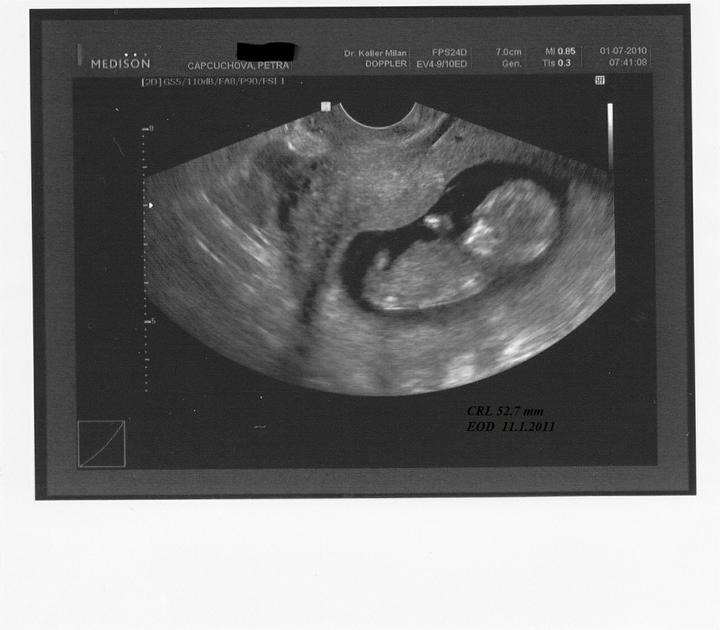

Bohužel se našel mezi mnou a přítelem určitý problém a bez odborné pomoci by jsme se vůbec nedočkali! Snad už se konečně zadařilo a našemu bobískovi, kterého mám v sobě, se bude u nás líbit a vydrží až do samého konce porodu 18.1.2011.

Při druhém pokusu jsme se s doktorkou dohodly, že nastoupím na dlouhý protokol, aby se mi vytvořilo víc kvalitních vajíček. Začala jsem stimulovat od půlky února a koncem dubna šla na odběr folikulů. A taky že to pomohlo, vytvořilo se víc kvalitních vajíček. V Sanatoriu jsem řekla embryologovi, jaký jsem měla posledně problém, a sama mi nabídla, že teda necháme PK na 5 dnů, aby viděli, jak se vyvýjejí a jak to zvládají. 1.5.2010 jsme si jeli do Prahy pro naše embroušky, dokonce vydrželi ještě další dva, které mi dali zamrazit do zálohy.

13.5. jsem byla na odběrech hcg, jehož hodnota byla 994, hodnota byla dost vysoka na 13. den.